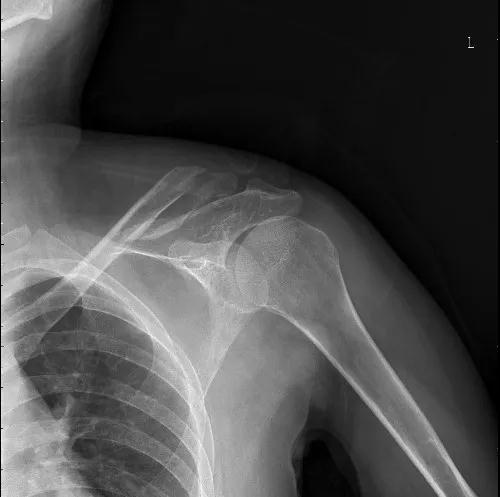

(锁骨骨折术前)